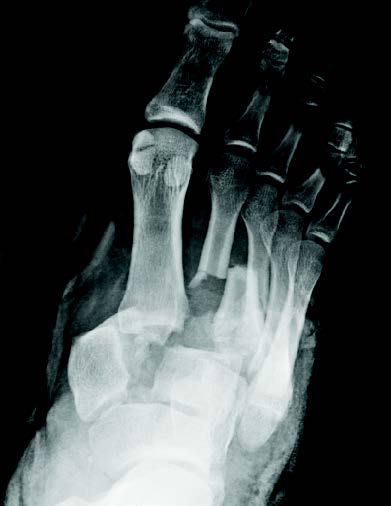

- Focus Area Reconstructive Surgery & Non-Surgical Management to Improve Bone Healing

- Sponsor DoD PRORP

- Primary Objective Observational study comparing outcomes following limb salvage versus amputation of a severe distal tibia, ankle, and/or foot trauma